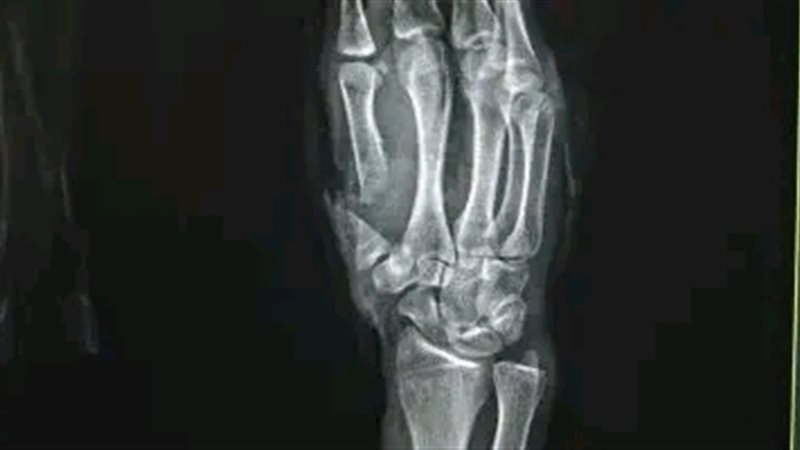

من جانبه أوضح الدكتور مجدي القاضي عميد كلية الطب البشري ورئيس مجلس إدارة المستشفيات الجامعية أن الفريق الطبي نجح في إعادة زرع إصبع الإبهام باستخدام جراحة ميكروسكوبية متقدمة استغرقت نحو 6 ساعات متواصلة جرى خلالها توصيل الشرايين والأوردة والأعصاب الدقيقة إلى جانب تثبيت عظام الإصبع بأسلاك معدنية ما أسهم في عودة الدورة الدموية واستقرار الحالة الصحية للمريض.